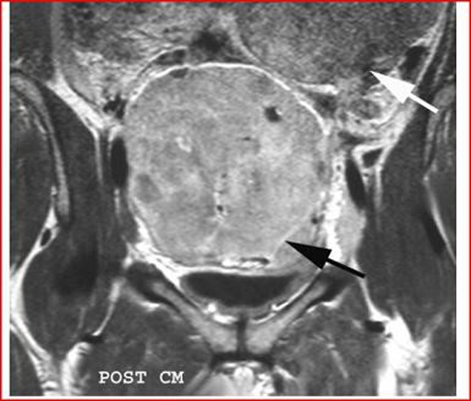

MRI shows a mass-free uterus, with no evidence of normal ovaries. The masses are approximately 13 cm in diameter and have low signal intensity on T1-weighted images and increased avidity after gadolin administration. On T2-weighted images the mass is hyperintense and the peripheral lesions probably correspond to ovarian follicles (Figures 4-6).

Figure 5: Coronal T1-weighted MRI image, performed by administration of intravenous gadolin, shows low signal intensity of the mass, the black arrow highlights an increase in the septal area. The second mass, white arrow, extends into the upper left quadrant.

Figure 6: Sagittal T2-weighted MRI image of the pelvis, shows that the ovarian mass posterior to the uterus has an heterogeneous, intermediate-high signal intensity, the follicles in the periphery (arrow points), have a high signal intensity. The asterisk highlights the free liquid in the Douglas cord.